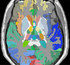

• RegLib C19 thumb all.png Case 19: Multi-contrast group analysis: intra- and inter-subject registration of multi-contrast MRI